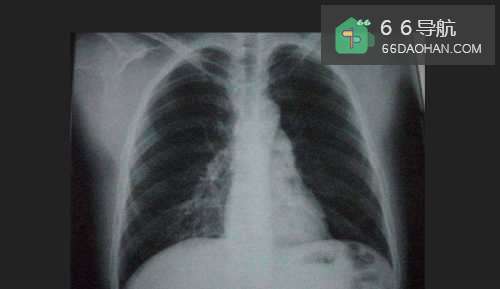

5第五种劝人戒烟的方法就是带他去意愿进行X光胸透体检,把拍出来的肺部胸透片给他看,一般吸烟的人肺部都是黑色的,让他害怕。

这种用心里战术的方法应该是最有效的。